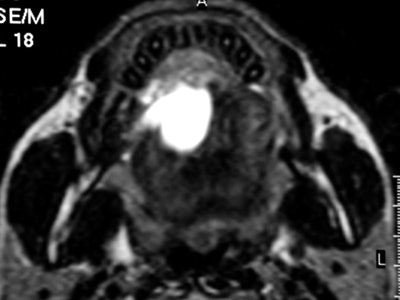

Contrast-enhanced coronal and sagittal T1-weighted images show a large, hourglass-shaped midline cystic lesion in the floor of the mouth splitting the genioglossus muscles. The diagnosis is a dermoid cyst. Images courtesy of Dr. Alexandra Borges.

Whenever imaging a malignancy, the full extent of the neck should be imaged for nodal staging. Bone windows are required for all cases of cancer staging and whenever dentomaxillary pathology is suspected.

Finally, she emphasized that when using MRI, it is crucial to instruct a patient not to swallow and to breathe quietly during the entire examination. The use of surface coils can be very helpful for the imaging of superficially located lesions such as the parotid and submandibular glands and the floor of the mouth.